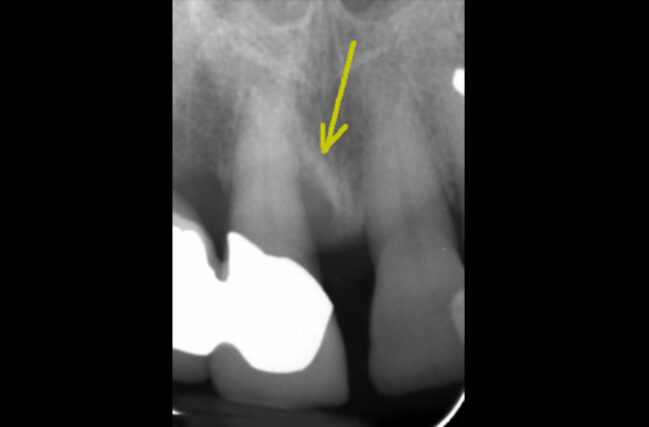

Periodontitis is the more severe form of gum disease, this is irreversible. Periodontitis involves the loss of supporting bone, as a result, in addition to the symptoms of gingivitis, it can also cause receding gums, gaps in between teeth, bad breath and wobbly teeth.